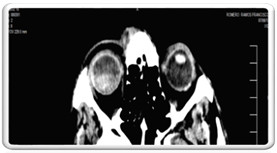

Por las características del cuadro clínico y los antecedentes patológicos del paciente se decidió realizar tomografía axial computarizada (TAC) de órbita, cráneo y senos perinasales.

TAC de órbita: cortes a 2-3 mm donde se observó aumento de la densidad del globo ocular derecho de localización posterior con nivel, densidad que osciló entre 34-60 UH, sugestiva de lesión sólida. Musculatura extrínseca con ligero engrosamiento de los músculos rectos lateral y medial. (Fig. 4)